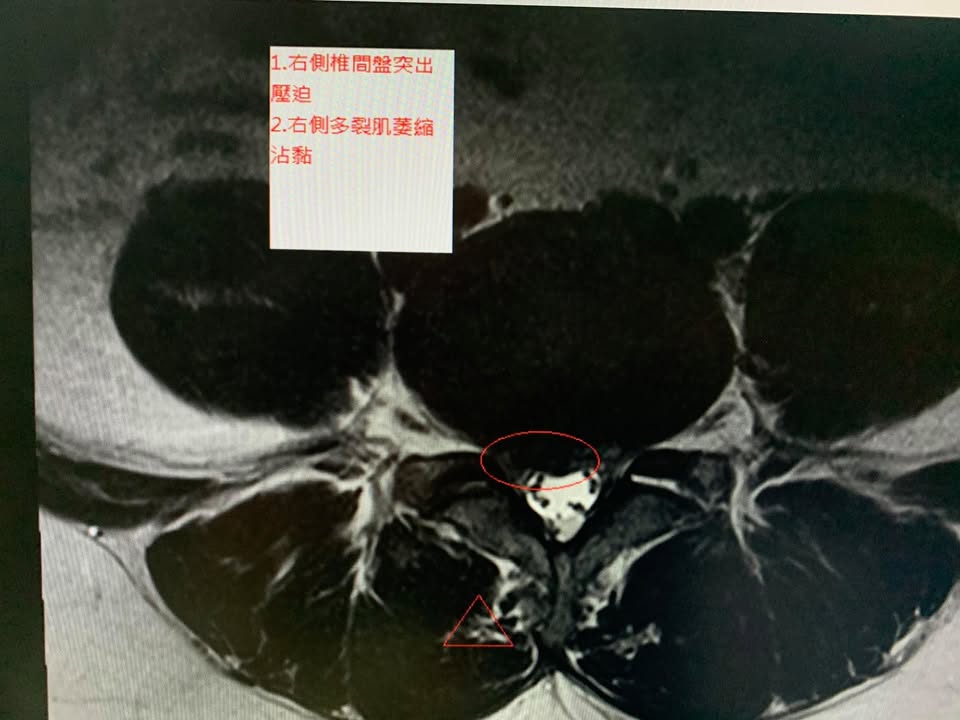

鄭先生抱怨右側大腿很痛,屁股也會痛,很酸痛,走路快沒辦法走下去,疼痛大約快一年,最後才去醫院拍攝MRI證實椎間盤突出症,L4L5突出,這中間已經做過物理治療拉了快三十次,效果不如預期,骨科醫師建議開刀,因為畏懼開刀,所以來接受脊椎整合中醫微創療法

✅診斷:椎間盤突出壓迫神經根

多裂肌萎縮